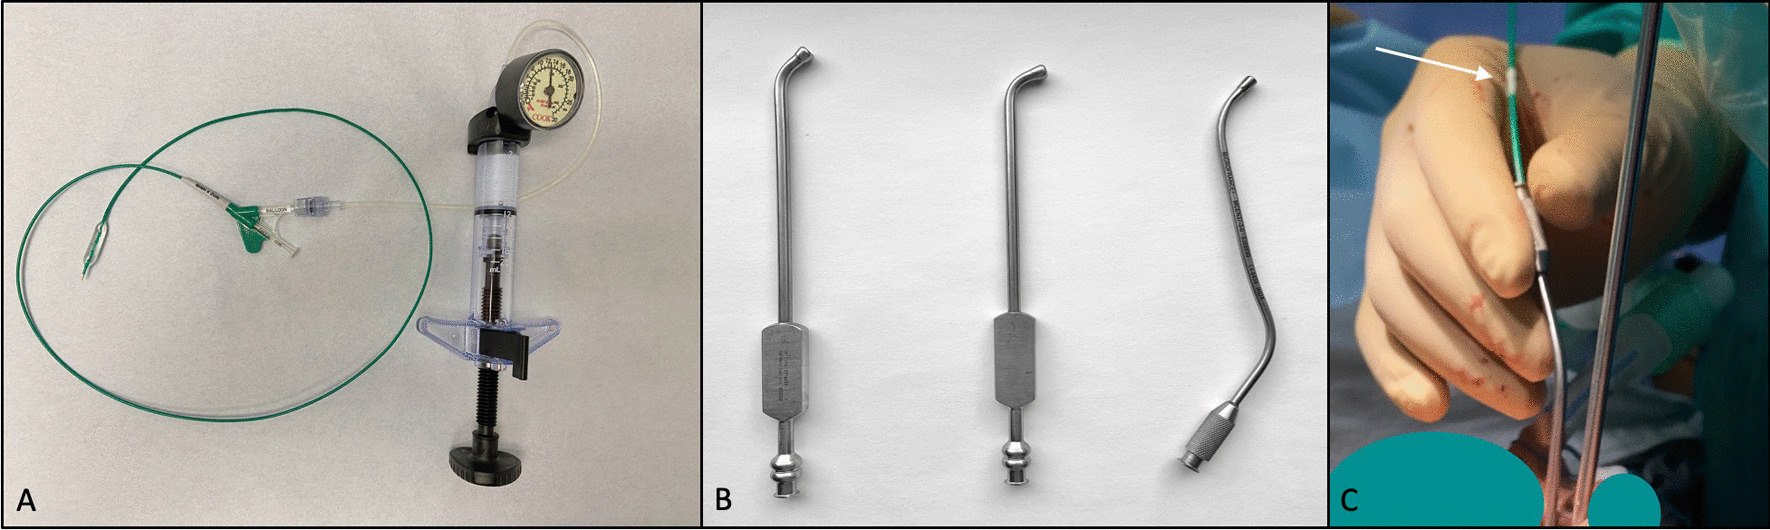

Fig. 2.

Intraoperative dilation of eustachian tube using an endovascular balloon. A–C Left orifice of the eustachian tube A the suction tip was brought to the orifice of the eustachian tube, the distal tip of the balloon could be visualized as white marker (solid arrow). B the suction tip was advanced slightly into the eustachian tube to facilitate insertion of the balloon. C the suction tip was retracted to visualize the distal end of the balloon—silver metal marker (dash arrow). D–F Right orifice of the eustachian tube during different steps of eustachian tube dilation. D the balloon was inflated to 12 atm after full insertion. E the balloon was deflated after 2 min. F the orifice is inspected after retraction of the entire system. The tip of the balloon (white) is visible